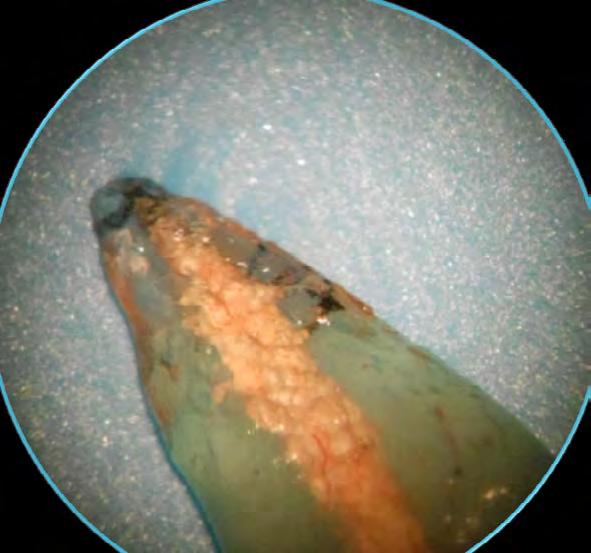

Figura 1. Muestra de control positivo, presentado un elevado nivel de filtración. Fuente: Directa.

Figura 2. Muestra de control negativo donde no presento filtración. Fuente: Directa.

Figura 3. Muestra obturada con gutapercha y Sealapex®. Fuente: Directa.

estos datos fueron convertidos a Las 5 muestras de control positivo presentaron filtración de tinta china de manera significativa (Figura 1), lo cual demuestra que es necesario el cemento sellador para obtener una obturación de conductos exitosa. Las muestras del control negativo no presentaron filtración de tinta china (Figura 2), demostrando que el barniz nos da confiabilidad con respecto al sellado radicular externo, evitando con esto la filtración de tinta por otras áreas que no fueran el ápice.

Se compararon los valores resultantes de las mediciones de los cementos selladores MTA Fillapex®, Sealapex® y Apexit plus ® (Tabla 1).

Comparación de los valores máximos y mínimos de la medición de la microfiltración.

Las desviaciones estándar más elevadas correspondieron al Sealapex® con DE=416.8 (Figura 3). el segundo lugar correspondió a Apexit Plus® con DE=505. (Figura 4).

Esto demuestra que existe amplia variación entre los valores de microfiltración del Sealapex y Apexit plus no así para el MTA Fillapex® mostró más homogeneidad entre sus muestras ya que la desviación fue DE=158.1 (Figura 5).

Valores mínimos y máximos de microfiltración en 3 materiales de obturación. (Micras) Tabla 1. Comparación de los valores máximos y mínimos de la medición de la microfiltración. Figura 4. Muestra obturada con gutapercha y Apexit Plus®. Fuente: Directa.

Figura 5. Muestra obturada con gutapercha y MTA Fillapex®. Fuente: Directa.